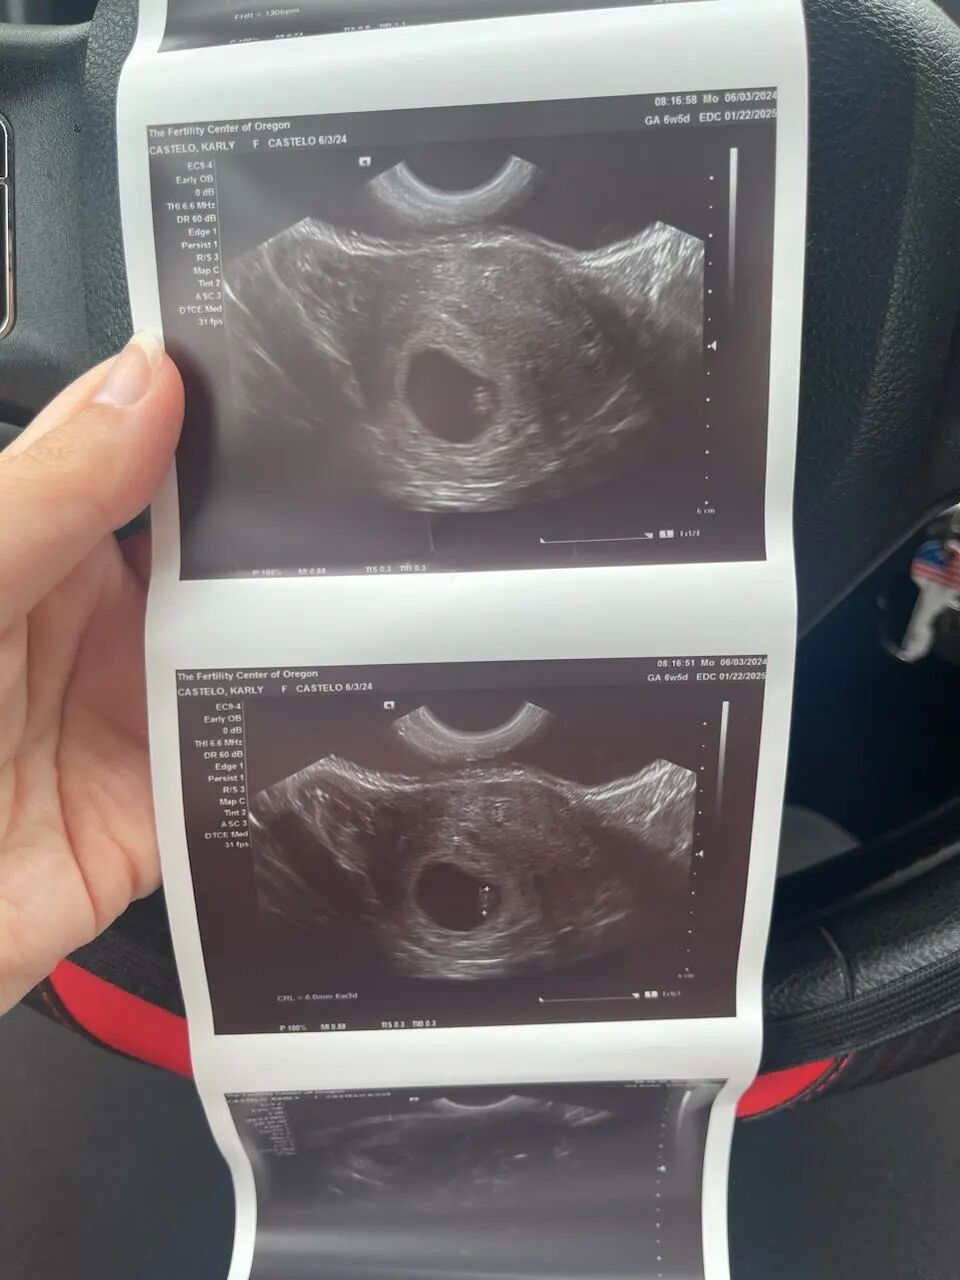

同样值得庆祝的是来自加州的爱妈A。她的首次B超检查也带来了令人欣喜的消息:胎婴儿已经发育到6周大!与她匹配的准父母来自国内,自体检开始至今,整个过程都非常顺利。爱妈A与准父母之间的配合默契,他们的孕期旅程一路绿灯,未来充满了更多的希望和期待。